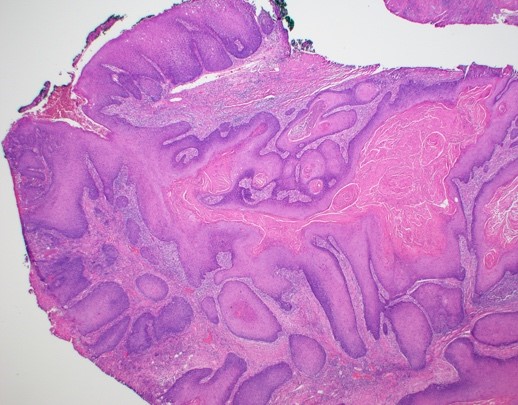

При хистопатологично изследване се установява че туморните лезии в началния стадий особено в повърхностните си части имат прилика с брадавици. Налице е хиперкератоза, паракератоза и акантоза. Кератиноцитите са еозинофилни и имат малки ядра. Хистологично по-голямата част от тумора е съставена от добре диференциран сквамозен епител. Екзофитната повърхност включва дълги папиломатози гънки, които обикновено са покрити от голямо количество орто- и паракератин. Последният покрива и дълбоката част на инвагинациите. Не съществува единно становище по въпроса дали верукозният карцином е самостоятелна нозологична единица или всъщност е екзофитна форма на спиноцелуларния карцином; в последно време обаче се приема че всъщност карциномите на покривния епител са само два типа - базоцелуларен и спиноцелуларен. Следователно верукозният карцином се класифицира към плоскоклетъчния карцином. В подкрепа на това становище е наличието на много смесени варианти - верукозен карцином, сред клетките на който се откриват гнезда от клетки на типичен плоскоклетъчен карцином - коекзистенция на два малигнени тумора. Много често се наблюдава и анапластична трансформация - първоначално се развива типичен верукозен карцином, който впоследствие се превръща в типичен плоскоклетъчен карцином. При наличие на гнезда на спиноцелуларен карцином биологичното поведение на тумора е потенциално по-малигнено в сравнение с вариантите без такива гнезда. Подтип на верукозния карцином е Epithelioma cuniculatum (Carcinoma cuniculatum или тумор на Ackerman по името на откривателя). Този тумор съдържа добре диференцирани епителни клетки с нисък клетъчен атипизъм. Има грапава повърхност и дълбоки инвагинации, изпълнени с кератин. Те навлизат на голяма дълбочина в съединителнотъканната строма, която е нежна и не съответства като количество на обилно разрастващия туморен паренхим.

Верукозен карцином - в много участъци образуванието наистина прилича на брадавица. Въпросът дали брадавиците са преканцероза и дали на базата им възникват малигнени тумори е все още дискутабилен. Все пак макроскопски и особено микроскопски верукозният карцином много наподобява брадавиците, както се вижда на хистологичните срезове. От там произлиза и названието на този тумор, който определено се класифицира към малигнените неоплазми. В миналото изследователите са оприличили верукозния карцином на verruca vulgaris и затова са го нарекли именно по този начин. Това обаче не бива да отключва канцерофобии у нито един пациент, тъй като брадавици има почти всеки индивид на планетата Земя и далеч не всяка от тях дегенерира в карцином - дори развитието на верукозен карцином на тази база е по-скоро казуистична рядкост. Хигиената, редовните профилактични прегледи дори само при общопрактикуващ лекар, избягването на алкохола и тютюнопушенето са достатъчни за превенцията на развитието на малигнени процеси в човешкия организъм.